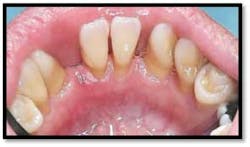

Tissue is light pink, tight and firm. All pockets are 1-3mm, no BOP

LR lingual post Tx and LL lingual post

Tissue is light pink, tight and firm. Pockets 1-3mm no BOP

Charting shows that all pockets are now generalized 1-3 mm with no BOP